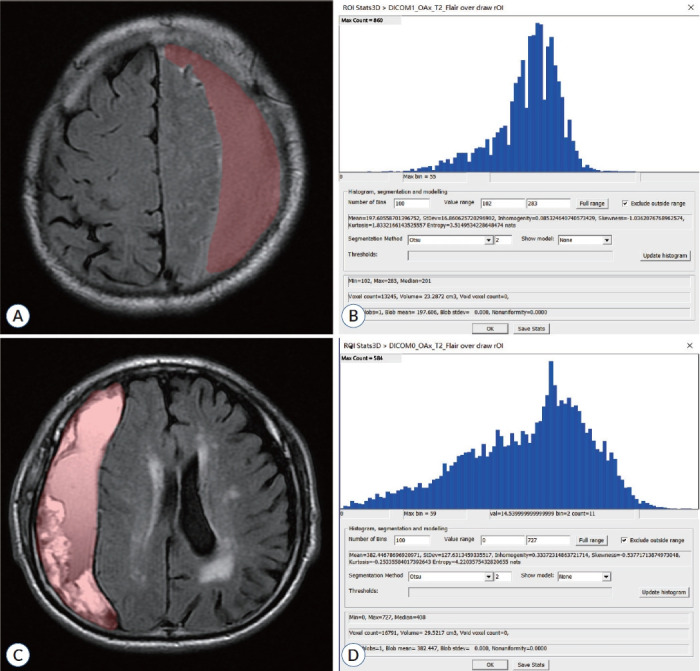

Methods: A total of 173 patients with CSDH who were hospitalized in our hospital from January 2018 to August 2023 were selected . All the patients underwent magnetic resonance imaging (MRI) examinations before surgery. According to whether patients with CSDH have relapsed after surgery, the patients are divided into recurrence group and non-recurrence group. FireVoxel software (https://firevoxel.org) was used to manually delineate the region of interest on the largest level of the hematoma cavity during MRI plain scans and measure the texture parameters. The texture parameters with statistical difference were analyzed by receiver operating characteristic curve.

Results: Heterogeneity and entropy texture parameters in the recurrence group were statistically different from those in the nonrecurrence group (p<0.05). When the cut-off point of the heterogeneity parameter was 0.284, the sensitivity, specificity, and accuracy of judging whether CSDH relapsed were 83.3%, 80.4%, and 80.7%, respectively.